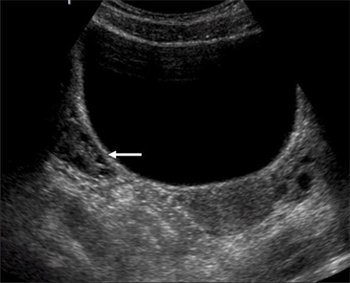

Los quistes ováricos son una de las afecciones más frecuentes en las mujeres de todas las edades. Aparecen afectando uno o ambos ovarios, sus tamaños van desde menos de 2 mm hasta decenas de centímetros y su número varía desde un solo quiste hasta incontables quistes.

Los quistes se forman en los folículos ováricos, los cuales son los encargados de producir el óvulo. Las ecografías convencionales muchas veces confunden estos folículos normales con quistes y muchísimas pacientes han sido operadas innecesariamente. |

Mira estas fotos: